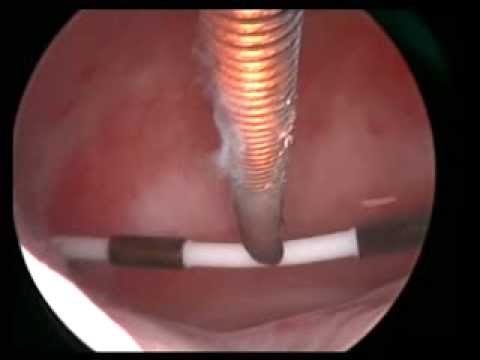

2)Histeroskopik Polipektomi veya Myomektomi :

Polip, rahim iç tabakasından ( endometrium ) kaynaklanan rahim içerisindeki alanı daraltan ve adet kanamasının fazla olmasına neden olabilen “et parçası” olarak tanımlanabilecek bir yapıdır. Normal yollarla veya tüp bebek uygulacak hastalarda gebelik şansını azaltacağı düşünülüyorsa histeroskopiyle çıkartılır.Hastanın kanama veya çocuk isteği olsun olmasın, poliplerin %1’inde kanser olasılığı olduğu için cerrahi olarak çıkarılması ( histeroskopik polipektomi ) ve çıkan parçaların mutlaka patolojiye gönderilmeleri önerilir.

Histeroskopik polip eksizyonu

Histeroskopik myomektomi